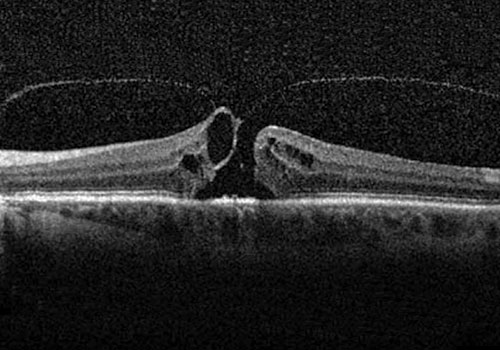

Il foro maculare è una patologia caratterizzata dalla formazione di una soluzione di continuo nella parte centrale della macula ed è associato ad una riduzione della capacità visiva.

Il foro maculare è sintomatico ed associato a calo visivo, metamorfopsie (distorsione delle immagini) o visione di una macchia scura centrale (scotoma).

Le adesioni vitreomaculari, i fori maculari lamellari e gli pseudofori possono rimanere asintomatici e non progredire. In questi casi è comunque consigliato eseguire periodicamente controlli del fondo oculare e un esame OCT. Una percentuale di casi tende invece ad essere sintomatica e a progredire nel tempo per cui si deve prendere in considerazione la possibilità di ricorrere ad un trattamento chirurgico.